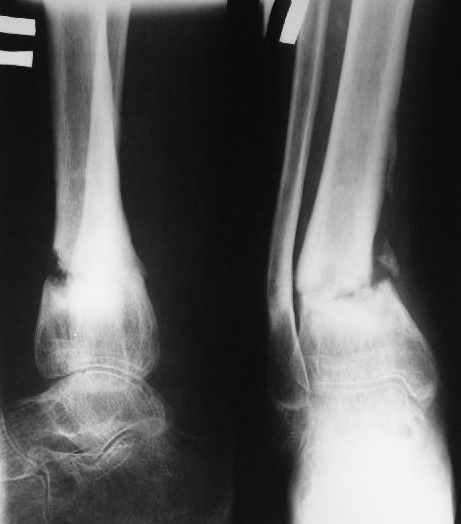

В январе 2005: варусная деформация н\3 голени, болевой с-м, комбинированная контрактура г\стопного сустава, нейропатия м\берцового нерва сохраняется слабость разгибания 1 пальца.

На данный момент ходит при помощи костыля (без присмотра -без костыля :), разрабатывает движения в г\стопном суставе.